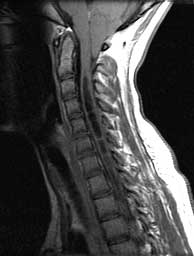

T1 sagittals pre gad

Septated CSF signal cavity expanding the cord from C3 down. Cerebellar tonsils herniated well below the posterior arch of C1.